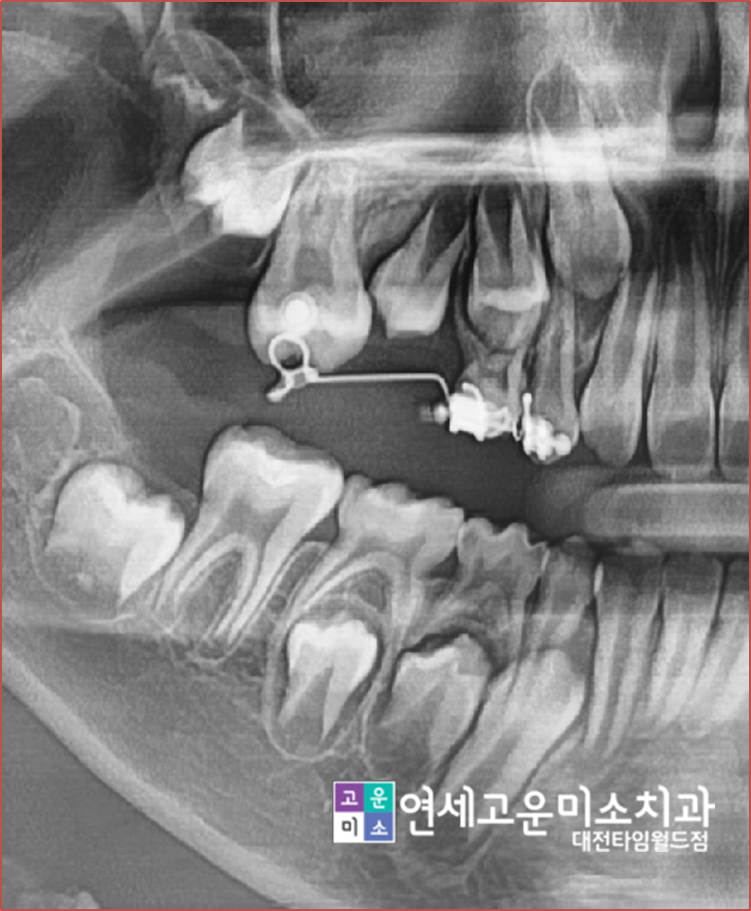

위에 엑스레이도 보면 큰 어금니가 앞으로 쓰러져서

나오면서 앞에 작은 어금니 나오는 공간을 점유했습니다.

이런 경우 그냥 방치가 되면 공간은

점점 없어지게 되고, 결국에는

발치교정을 해야 되는 경우가 발생합니다.

이 환자분은 간단하게 저 부위만 부분교정을 해서

앞으로 쓰러진 영구치를 원래 제 위치로 보내고

작은 어금니가 날 공간을 확보하는 작업을 시작하였습니다.

공간은 성공적으로 확보가 되었고

작은 어금니도 제 자리에 잘 나온 것을

확인할 수 있습니다.

기간은 1년 정도 소요되었습니다.